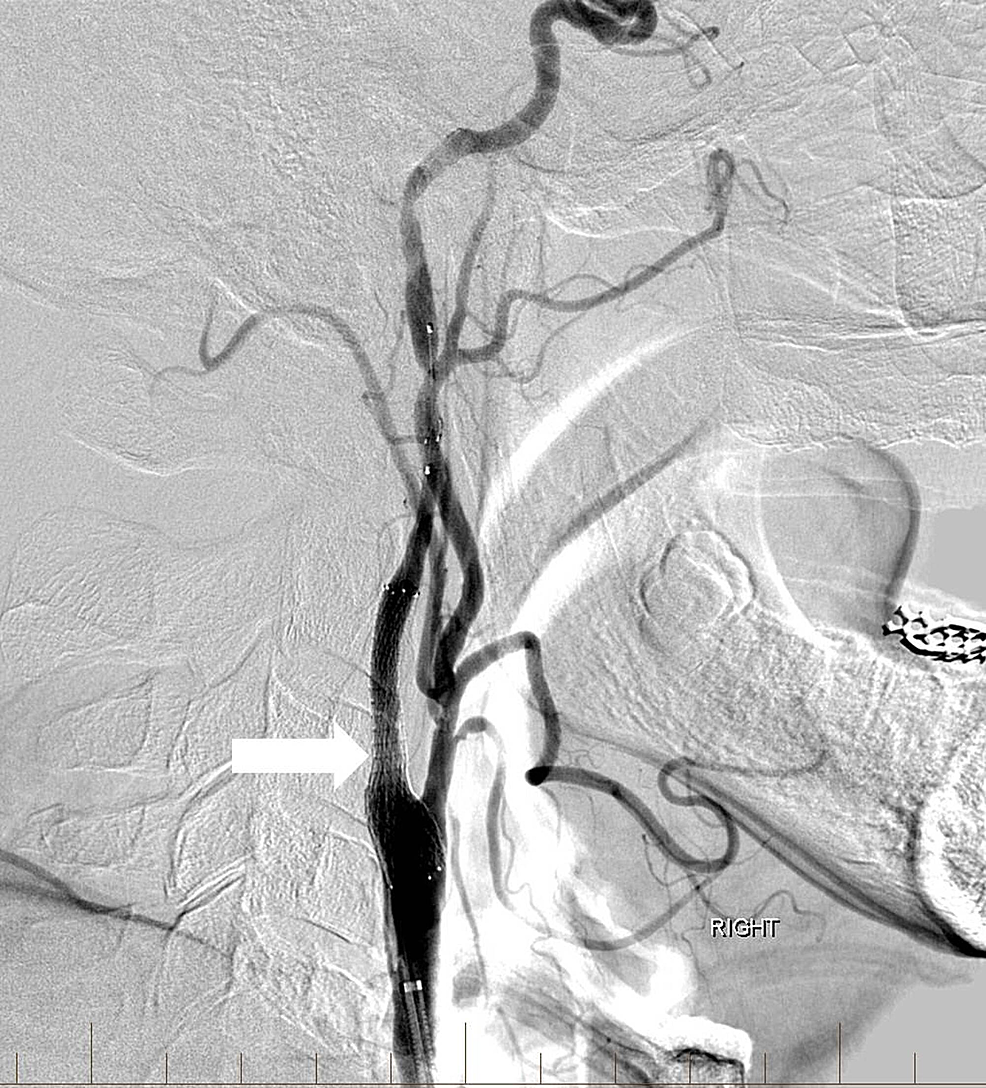

tPA was administered intravenously, and the patient was transferred to the interventional neuroradiology suite. Biplane digital subtraction angiography revealed a complete occlusion of the cervical right ICA at the vessel’s origin due to extensive atherosclerotic disease (Figure 6).